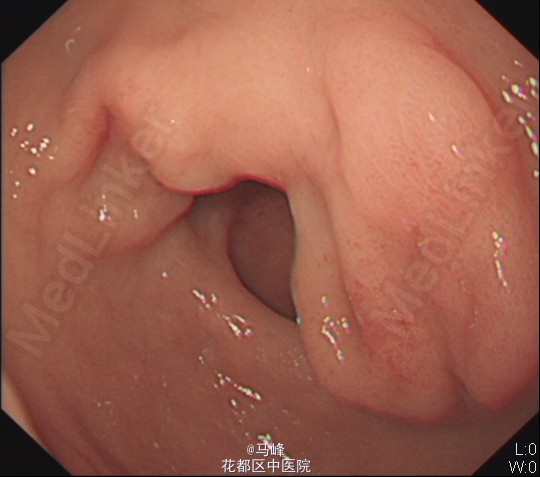

中年男性,主诉:反复上腹痛1年余,再发并加重4天。 现病史:患者1年余前无明显诱因出现上腹部隐痛,伴反酸、腹胀,自服制酸药后腹痛可缓解。后腹痛反复发作,未予重视。4天前无明显诱因上腹痛再发,表现为烧灼样,绞榨样疼痛,自服制酸后腹痛不能缓解,遂来我院。

查体:生命体征平稳。腹平软,上腹压痛明显,无反跳痛,肝脾肋下未及。

入院后行胃镜检查,见胃窦、十二指肠各有一溃疡病灶。HP(+) 诊断:消化性溃疡(复合性) 入院后予PPI+阿莫西林+克拉霉素抗HP治疗。